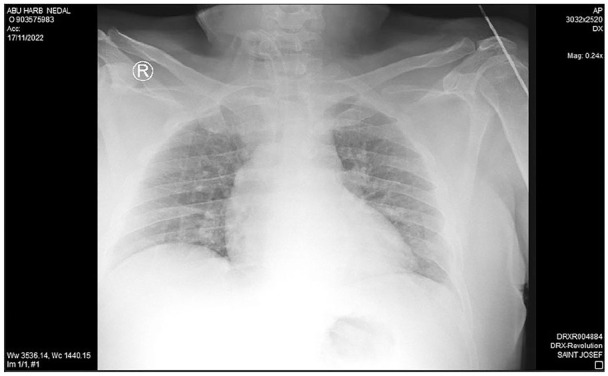

Case presentation: A 43-year-old male, with a tracheostomy tube in place for 8 years following a neck blast injury, presented with a foreign body in his airway. Chest X-ray revealed a fractured metallic tracheostomy tube lodged in the left main bronchus. The tube was successfully removed by rigid bronchoscopy under general anesthesia, and the patient was discharged in good condition with a new tracheostomy tube.